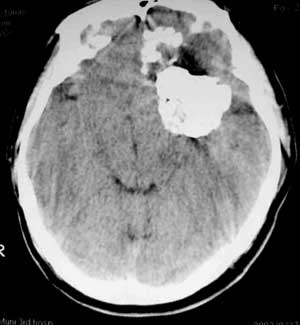

男性,60岁,反复癜痫40余年。

病理结果

骨软骨瘤